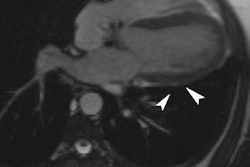

On the island, 1 in 7 residents has chronic kidney disease, and the condition is particularly prevalent among Japanese, Filipino, and Native Hawaiian residents, according to the company. Research led by Kevin Bennett, PhD, who has developed a special contrast agent for use with the system, will focus on why these particular ethnic groups are more prone to the disease.